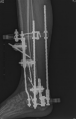

患者平臥位,消毒鋪巾后,應(yīng)用一個半環(huán)連接患側(cè)跟骨骨牽引針,然后通過一個連接器將半環(huán)與CO接骨機(jī)器人中間臂相連接,分別應(yīng)用兩個半環(huán)與CO接骨機(jī)器人其他兩個臂相連,完成復(fù)位裝置組裝,通過機(jī)器人操控桿逐步調(diào)整器械臂的力進(jìn)行牽引復(fù)位,糾正骨折斷端嵌插,左右夾擠,糾正側(cè)方移位,C臂監(jiān)視下見脛腓骨遠(yuǎn)端骨折斷端移位糾正,力線良好。在CO接骨機(jī)器持續(xù)牽引下,于脛骨中段及跟骨分別植入一根克氏針,連接CO外固定架維持牽引,松開機(jī)器臂對骨折端的牽引及夾擠力,于脛骨中下1/3處置入骨針,內(nèi)下方及外上側(cè)分別置入一根骨針對骨折塊進(jìn)行撬撥復(fù)位,C臂再次透視見脛腓骨遠(yuǎn)端恢復(fù)解剖力線,關(guān)節(jié)面無臺階,內(nèi)植物位置及形態(tài)良好?;顒右姽潭ɡ喂?。無菌敷料包扎釘?shù)溃中g(shù)結(jié)束。術(shù)中出血約100ml。手術(shù)時長2小時。

圖1 術(shù)中操作及影像資料